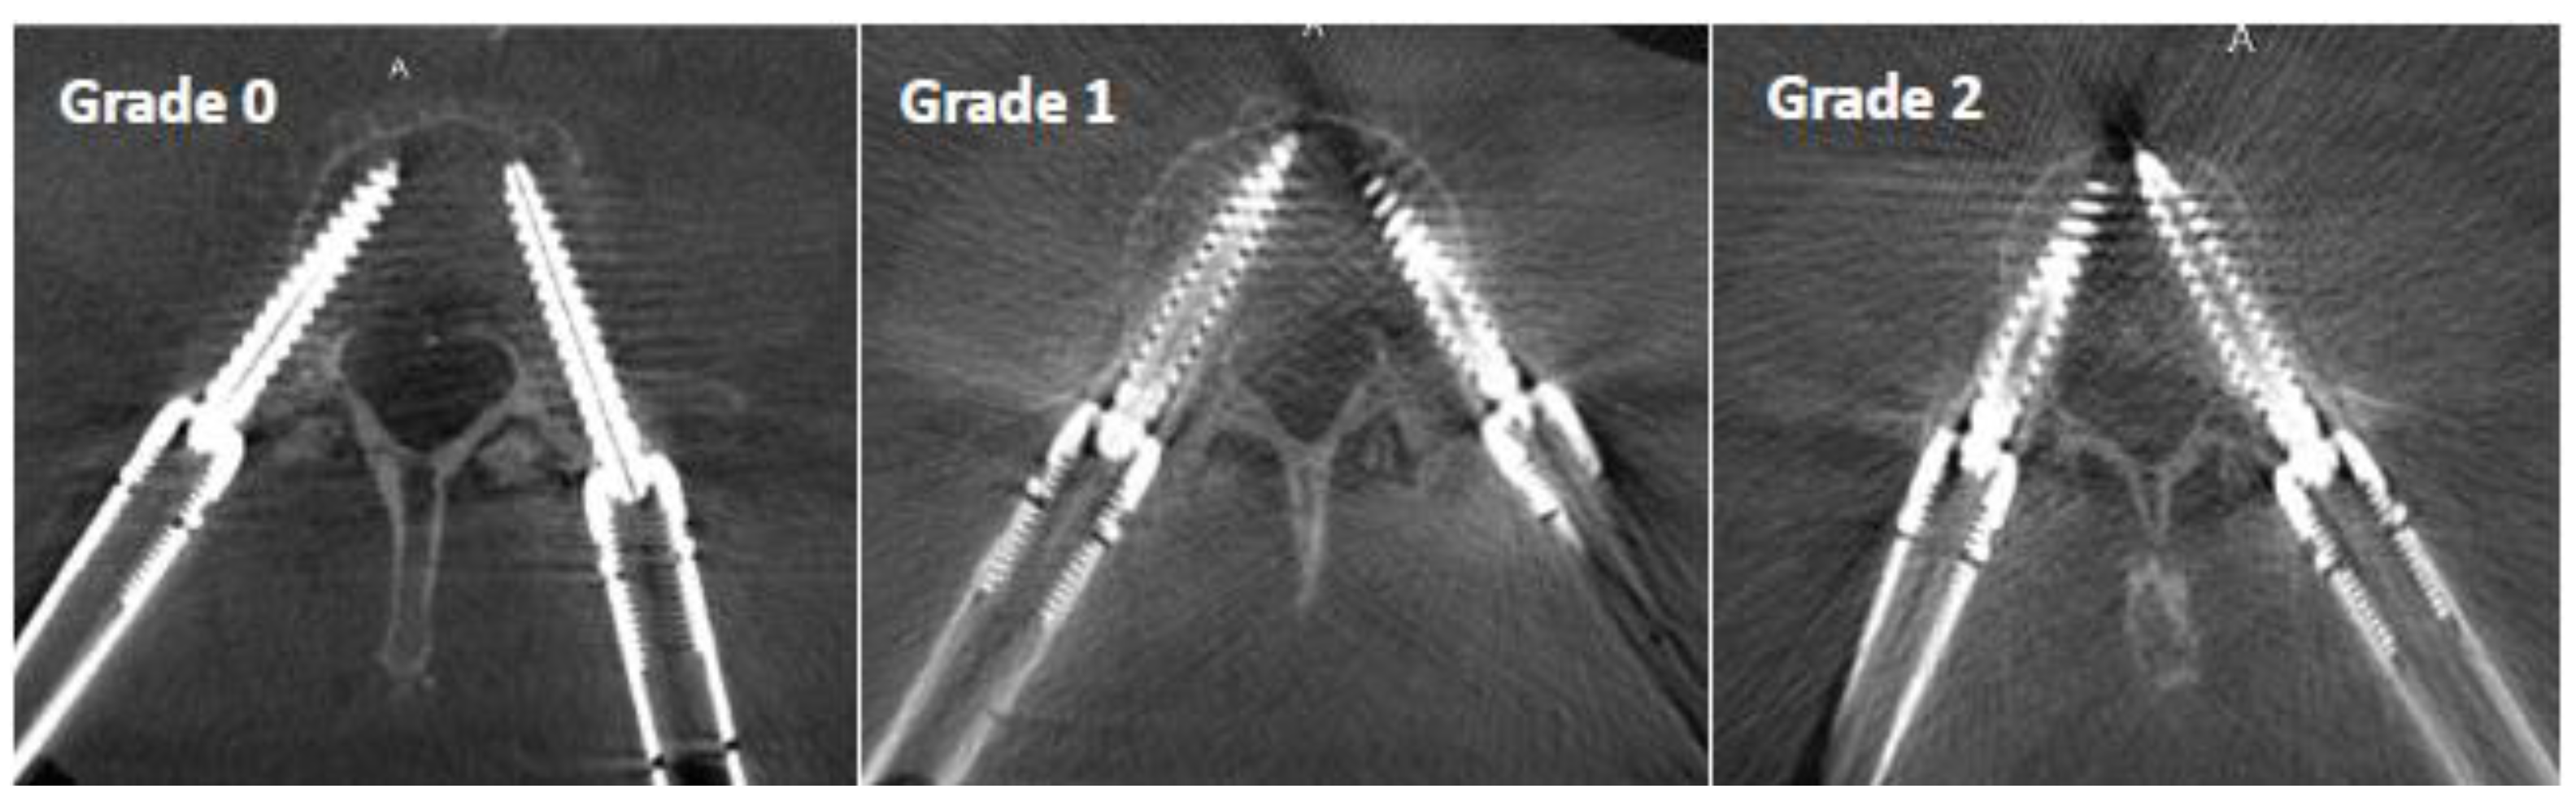

- Grade 0: mild artifact, screw thread clearly visible, cortical bone clearly visible, bone soft tissue interface clearly visible, clear interpretation possible;

- Grade 1: moderate artifact, screw thread visible, cortical bone with unclear portions, bone soft tissue interface distinguishable, interpretation possible;

- Grade 2: strong artifact, screw thread unclear, cortical bone contours unclear, bone soft tissue not distinguishable, interpretation difficult.